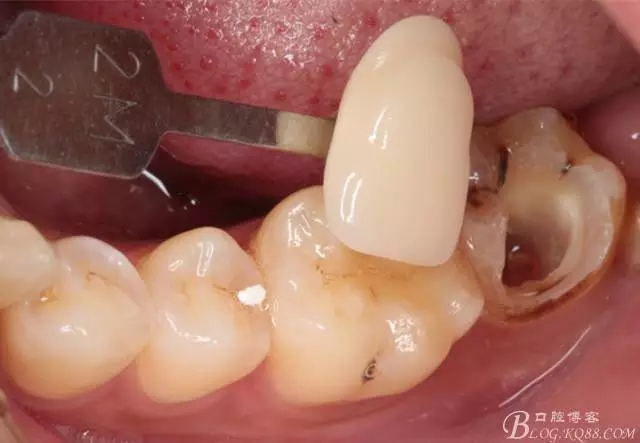

流動樹脂充填窩洞,金霸王車針和鎢鋼車針常規(guī)備牙,配合硅膠尖拋光,頰側(cè)排00排齦線。硅橡膠二次法取模,記錄咬頜關系,臨時樹脂充填窩洞。

一周后復診,37臨時充填物完好。去除臨時充填物,清潔基牙,試戴嵌體,就位良好,邊緣密合。取下嵌體,常規(guī)處理,9.5%HF處理20S,沖洗一分鐘,95%酒精蕩洗5分鐘?;劳磕?7%的磷酸凝膠,釉質(zhì)區(qū)域酸蝕30S,本質(zhì)區(qū)域15S。粘固用的是3M第八代粘接劑套裝,照說明書逐步操作。最終固化時涂滿阻氧劑,每個牙面最少光照30S,光固化燈用漸強模式。常規(guī)調(diào)合,配合硅膠尖套裝拋光。術后常規(guī)醫(yī)囑,不適隨診。